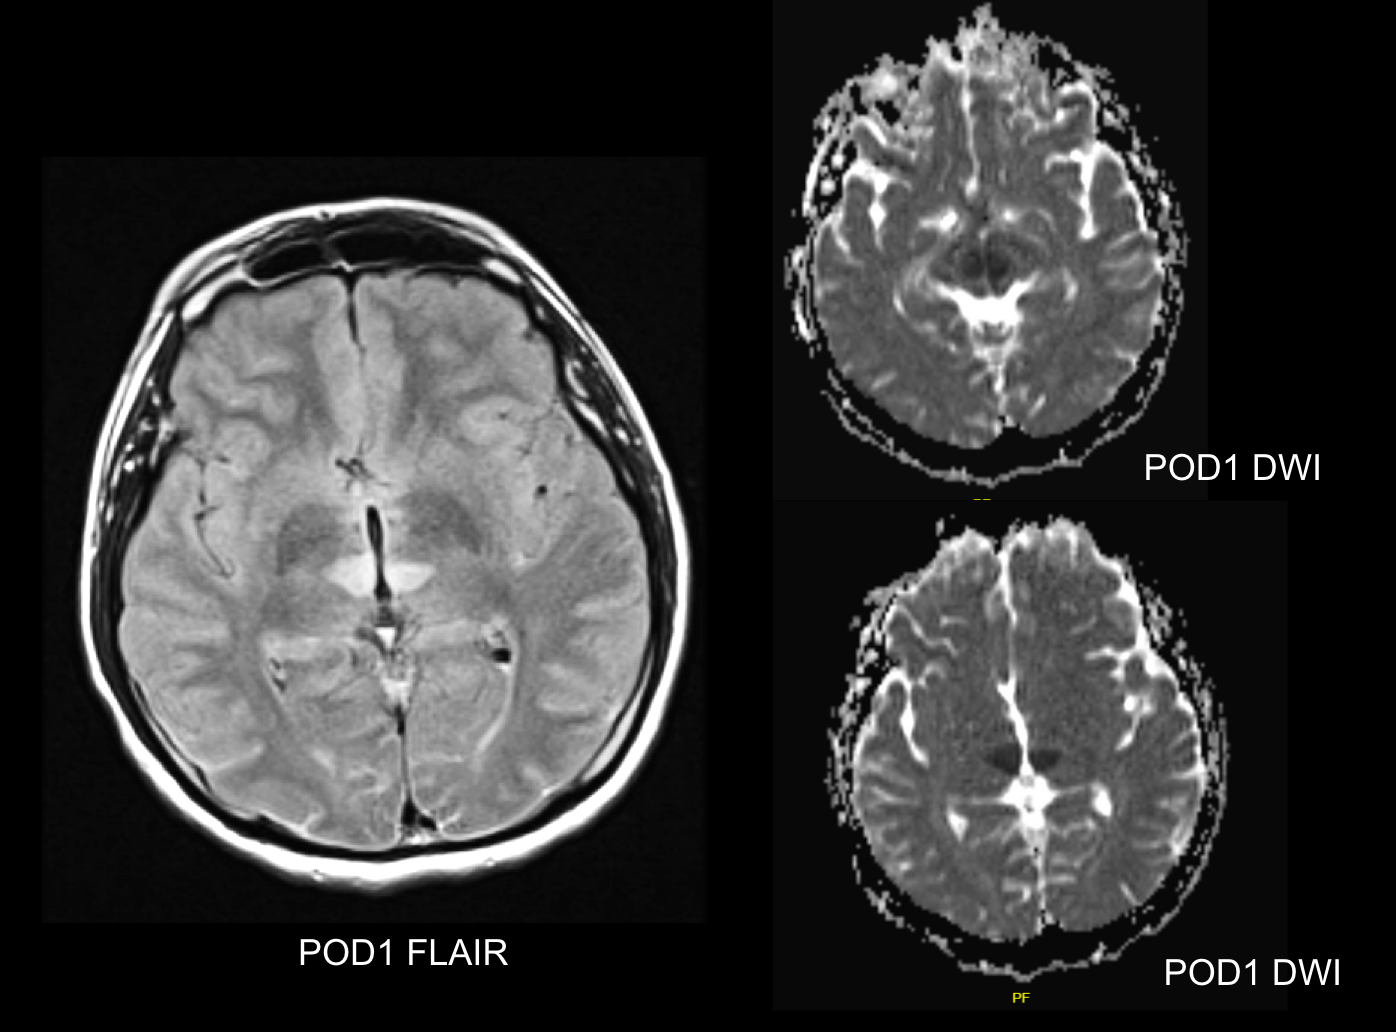

Background

This study explored whether Myelin Water Imaging could detect myelin injury in Anti-NMDA receptor autoimmune encephalitis (NMDAr-AIE), where traditional neuroimaging is often normal. Myelin Water Fraction (MWF) quantifies myelin content by distinguishing myelin sheath water from other brain water compartments.

Methods

Adult participants with confirmed NMDAr-AIE diagnoses and healthy controls (HC) underwent 3T brain MRI (Magnetic Resonance Imaging) including MWF mapping. Participants were recruited after discharge from the hospital. Mean MWF was calculated for 4 white matter regions of interest (ROI). MHI (Myelin heterogeneity Index) was calculated by dividing the MWF standard deviation by the mean MWF. Patient demographics, clinical assessments, treatment, and outcomes were collected.

Results

Fig. 1 Myelin Water Imaging of two selected patients

Screenshot 2025 06 01 at 12.05.23 pm

Myelin Water Imaging showed no myelin pathology in five NMDAr-AIE patients, with MWF and MHI values comparable to HC, suggesting that myelin pathways are relatively preserved post-recovery from AIE. Moving forward, we aim to continue recruiting healthy controls, patients post-recovery and those experiencing active disease to determine if there are any MWF abnormalities throughout the disease course. Future studies are needed to assess MWF changes in other antibody-mediated encephalitides.